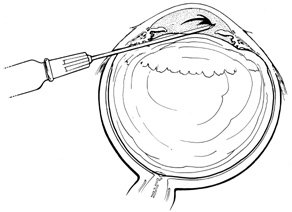

Current cryotherapy instrumentation employs expansion of high-pressure nitrous oxide at the tip of a probe generating temperatures as low as 89°C. The temperature effect is confined to the tip of the probe by an insulating sleeve. A probe 2.0 to 2.5 mm in diameter usually is used for retinal work. Treatment of retinal breaks and pathologic conditions requires accurate placement of the cryoprobe tip. The surgeon must be certain that the indentation visualized with the indirect ophthalmoscope is the tip of the probe and not the shaft. Confusion between the tip and the shaft of the cryo-probe can cause inadvertent posterior freezes.33 To minimize the possibility of this complication, the surgeon must indent only with the tip of the cryoprobe (Fig. 10). It is also helpful to perform the first freezes at the most anterior aspect of the area requiring treatment to assess both location and intensity of treatment.

Fig. 10. A. Inadvertent posterior placement of cryoprobe tip caused by visualization of cryoprobe shaft. B. Correct placement of cryoprobe tip.